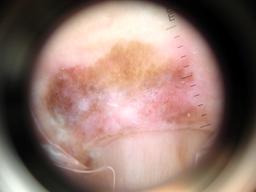

{

"age_approx": 80,

"anatom_site_general": "anterior torso",

"concomitant_biopsy": true,

"dermoscopic_type": "contact non-polarized",

"diagnosis_1": "Malignant",

"diagnosis_2": "Malignant melanocytic proliferations (Melanoma)",

"diagnosis_3": "Melanoma in situ",

"diagnosis_confirm_type": "histopathology",

"family_hx_mm": false,

"image_type": "dermoscopic",

"mel_thick_mm": "0.00",

"melanocytic": true,

"patient_id": "IP_4057359",

"personal_hx_mm": false,

"sex": "male"

}